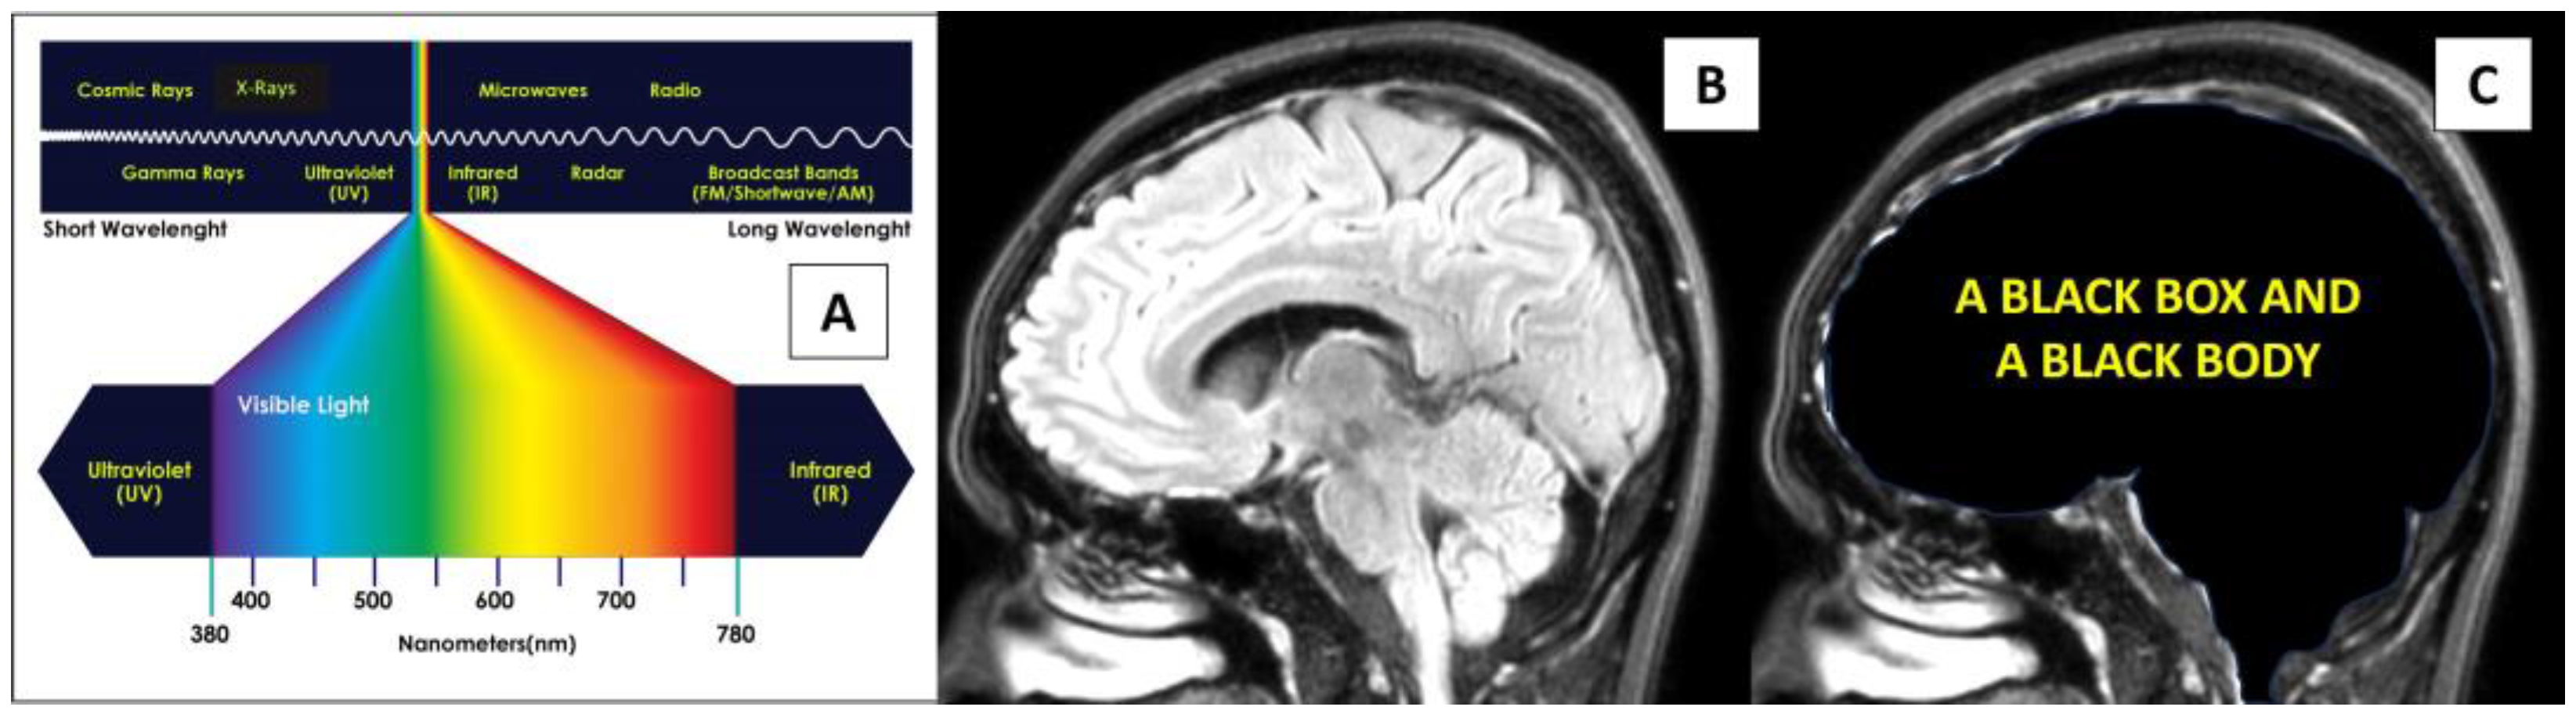

2.2. Awake Brain Surgery—Marked and Rapid Brainwave Changes When the Brain Was Directly Exposed to Different Wavelengths of Light

3.1. Physics Perspective on Direct Light Energy onto the Brain